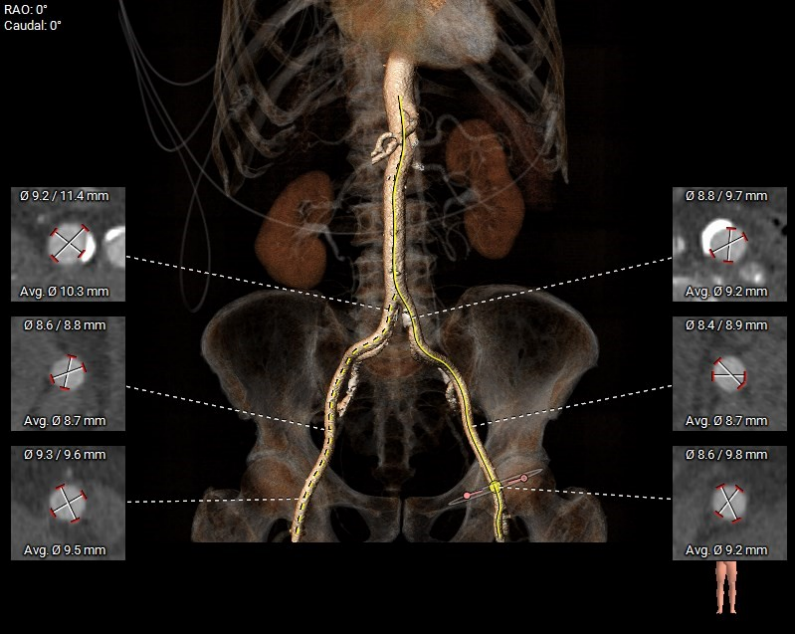

· 腹主-双侧髂总动脉少量钙化斑块分布,股-髂动脉走行、内径可,穿刺点附近无钙化分布

图6. 腹主-双侧髂总动脉少量钙化斑块分布,股-髂动脉走行、内径可,穿刺点附近无钙化分布。